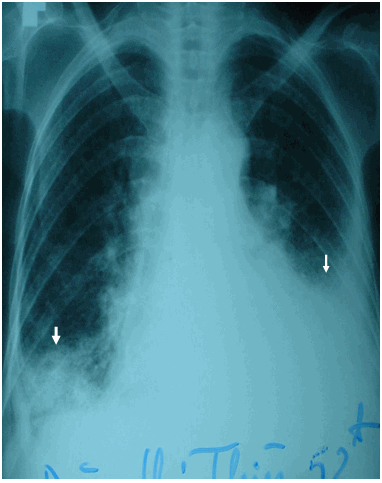

Hình ảnh viêm phổi có tràn dịch màng phổi hai bên trên phim phổi thường ở bệnh nhân nữ 52 tuổi - Viêm phổi gây tràn dịch màng phổi ở bệnh nhân Collagenose

Viêm phổi, phổi bị nhiễm trùng rồi vi trùng lan ra màng phổi hoặc vùng phổi bị nhiễm trùng quá gần màng phổi làm màng phổi bị kích thích tiết ra dịch.